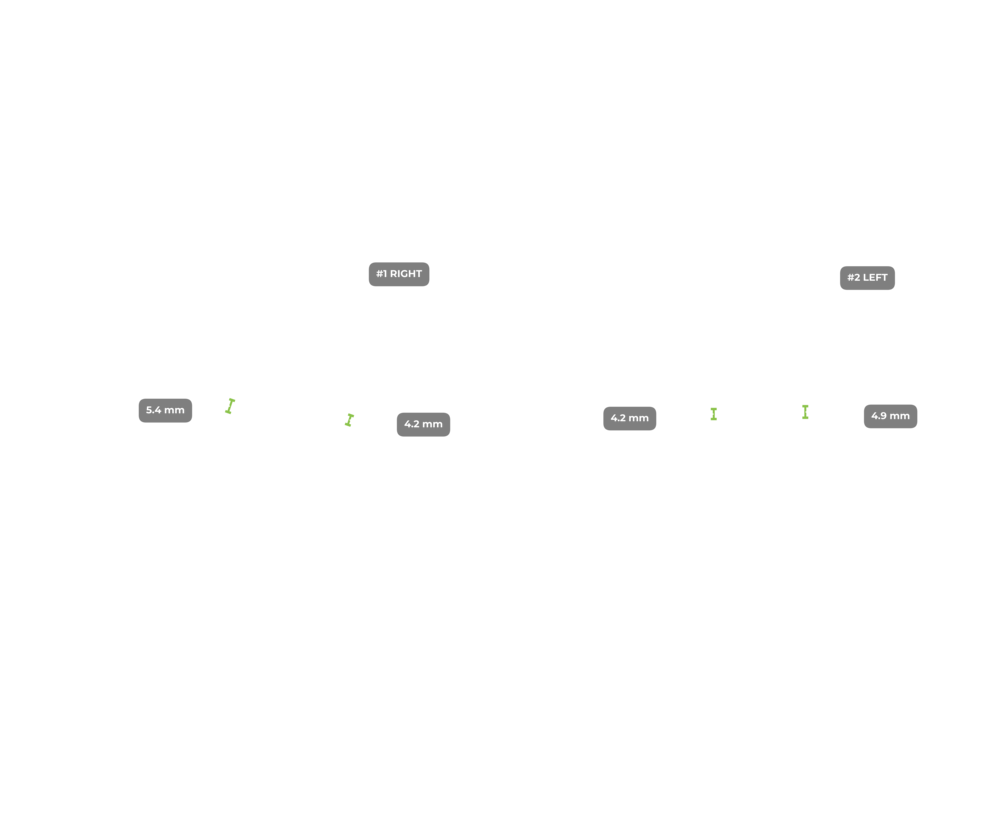

ИИ и алгоритмы интеллектуального анализа для рентгена коленного сустава. Оцените дегенеративные процессы менее чем за 1 минуту